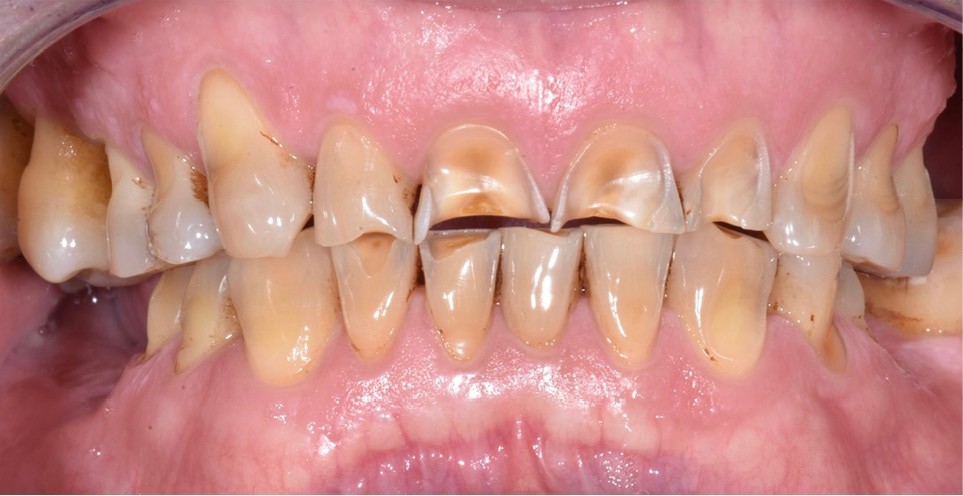

Le cas clinique présenté ici illustre cette démarche thérapeutique. À la suite d’un diagnostic de cancer des voies aérodigestives supérieures, un patient de 68 ans a bénéficié d’un traitement par radiothérapie cervico-faciale, terminée depuis plus de 2 ans. Il souhaite désormais retrouver une réhabilitation fonctionnelle et esthétique de sa cavité orale. Il indique que le délabrement de ses dents antérieures est à l’origine d’un important préjudice esthétique, qui l’a conduit à ne plus sourire. De plus, ses dents absentes réduisent fortement ses capacités masticatoires. Ces différents facteurs influent donc directement son estime de soi et sa qualité de vie, paramètres clés de la rémission dans le cadre oncologique. À l’examen clinique, il présente une perte de calage postérieur, avec des édentements terminaux secteur 2 et 4, ainsi que de volumineuses pertes de substance au niveau des dents présentes (fig. 1).

Bien qu’étant à l’initiative de sa propre prise en charge, le patient reste très anxieux lors de la réalisation des soins, en raison de ses antécédents locaux. Dans ce contexte, une prise en charge thérapeutique conciliant des restaurations partielles collées et des prothèses amovibles à châssis métallique a donc été réalisée, en tâchant d’optimiser la séquence thérapeutique pour limiter le nombre de séances et maintenir la coopération du patient. Nous détaillerons ici les étapes clés de la réalisation des éléments collés.